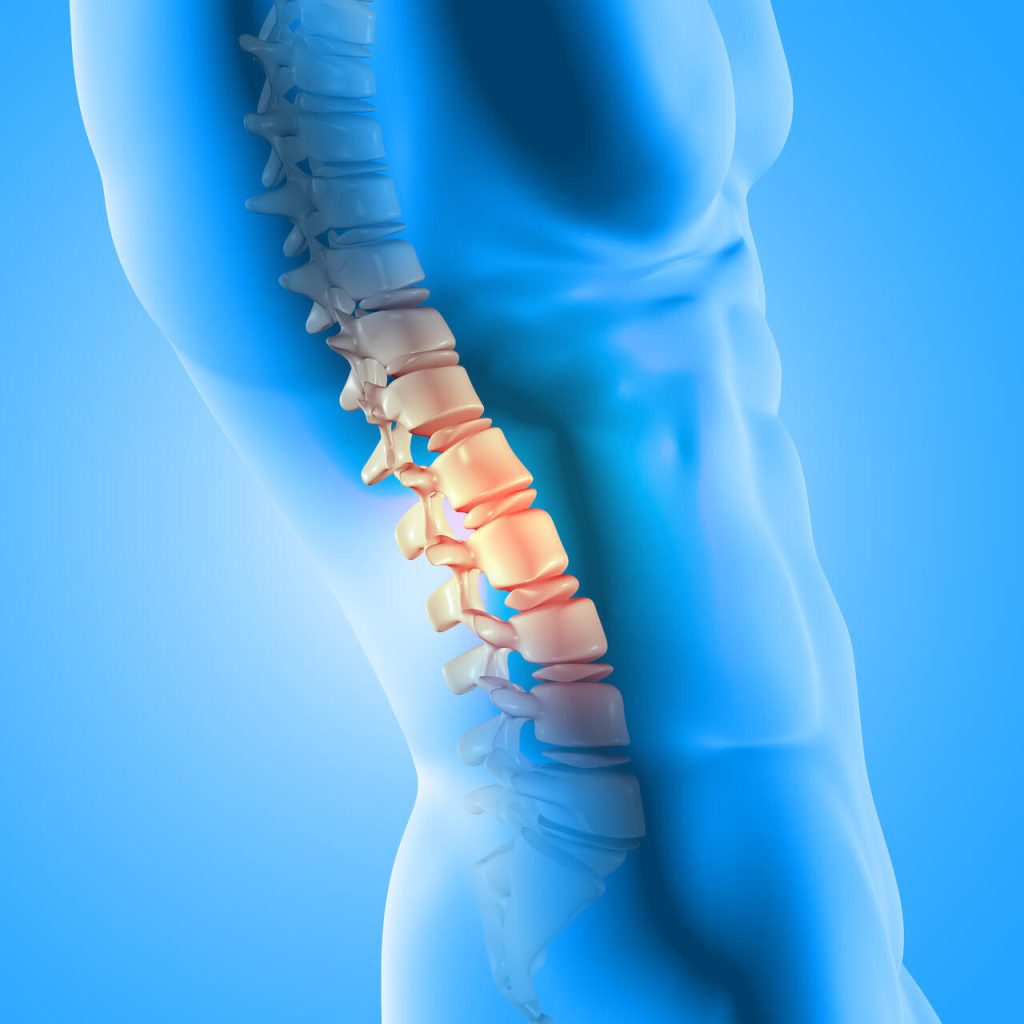

A cirurgia endoscópica da coluna é uma abordagem inovadora e minimamente invasiva para tratar uma variedade de condições. Diferentemente dos procedimentos convencionais, essa técnica utiliza um endoscópio, um tubo fino e flexível com uma câmera acoplada, para acessar a área afetada através de pequenas incisões.

Ela é indicada para tratar hérnias de disco, estenose espinhal, espondilolistese e alguns casos de compressão nervosa causada por problemas estruturais. Além disso, pacientes com dor crônica na coluna que não responderam bem a tratamentos conservadores podem se beneficiar dessa opção menos invasiva.

Os benefícios deste procedimento incluem menos danos aos tecidos ao redor, menor tempo de recuperação e redução no risco de complicações. Além disso, a internação hospitalar é geralmente mais curta, permitindo que os pacientes retomem suas atividades diárias rapidamente.

A cirurgia endoscópica da coluna é uma opção promissora para muitos, já que alivia a dor e melhora a qualidade de vida.